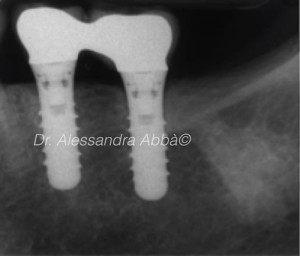

Treatment of peri-implantitis: evaluation of post-operative pain

Implant treatment has become a popular option for patients who have lost one or more teeth. As a result of this, more implant related infections occur....

INTRODUCTIONEarly implant failures typically occur before or at the abutment connection and are generally associated with minor peri-implant bone loss. Late implant failures, in contrast, occur...